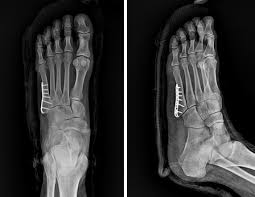

또한, 복합 골절이나 압박 골절과 같이 더 복잡한 경우에는 수술이 필요할 수 있으며, 뼈가 조각나거나 비스듬하게 부러진 경우에는 금속판을 추가적으로 사용할 수 있습니다.

- 수술 치료: 뼈가 심각하게 파열되거나 개방성골절인 경우 수술이 필요합니다. 이 경우 수술비용은 약 60만원에서 150만 원까지 다를 수 있으며, 이 비용에는 입원비, 식비, 약값 등이 포함될 수 있습니다.